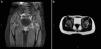

The patient was admitted for suspected septic arthritis of the hip, and empirical antibiotic treatment with cefotaxime and clindamycin was initiated. An ultrasound scan was performed that revealed bilateral effusion in the coxofemoral joints. At admission, complete blood count was normal, C reactive protein (CRP) level was 172mg/L and erythrocyte sedimentation rate (ESR) was 94mm/h. Arthrocentesis was performed to collect joint fluid, which had 32,000cells/mm3 with 90% of polymorphonuclear leukocytes. Joint fluid and blood cultures were negative. Magnetic resonance imaging did not reveal involvement of the bone or surrounding soft tissues (Fig. 1). Chest radiography, echocardiography, antistreptolysin O titre, peripheral blood smear and funduscopic exam were all normal. Rheumatoid factor, antinuclear antibodies and the Mantoux test were negative. Parvovirus, Coxiella and Brucella serology tests were negative. An intermittent fever of up to 38°C persisted in the early days, and subsequently the patient remained afebrile with improvement of hip mobility and pain, so she was discharged with oral ibuprofen and transitioned to outpatient follow-up. A year later, she developed arthritis of the left hip again, with elevated CRP (75mg/L) and intermittent low-grade fever in a self-limited course that lasted 10 days. Later on, she experienced joint inflammations that subsided after 24–48h in the ankle, proximal interphalangeal (PIP) joint and hip. Genetic testing for FMF was requested, detecting the heterozygous mutation p.A744S in exon 10 of the MEVF gene.